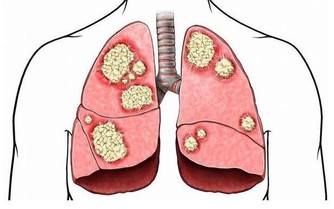

肝臟是人體中排毒解毒的重要器官,也是人體中最大的消化器官,生活中許多肝病患者是由於過度飲酒導致的,過度飲酒會增加肝臟以及腸胃的負擔,肝臟在人體內非常脆弱,起初患肝病,人體並沒有明顯症狀,因此,很多人錯過了治療肝臟最佳時期,當肝臟疼痛的時候,往往代表肝臟已經受損嚴重,生活中我們應該及時發現身體不適,定期去醫院做檢查,及時發現,及早治療。

肝臟不好的人,還會出現這些表現

1、皮膚出油,皮膚乾燥,頭髮容易出油

2、背部長大量粉刺,且背部容易出油

3、面色發黃,體形消瘦,牙齦出血

4、尿液發黃,尿液起沫,鞏膜發黃

5、眼睛乾澀,早晨起床眼屎多

6、食慾不振,腸胃消化不良,經常便秘

7、面色發黑,身體出現蜘蛛痣,肝掌